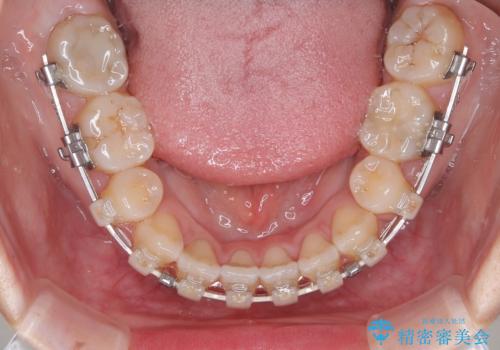

- 矯正装置

- 審美装置

- 1年6ヶ月

上下左右の第一小臼歯4本を抜歯し、ワイヤー装置にて矯正治療を行うこととしました。

舌のトレーニングをしっかりと行ってくださり、1年半という非常に短い期間で仕上げることができました。